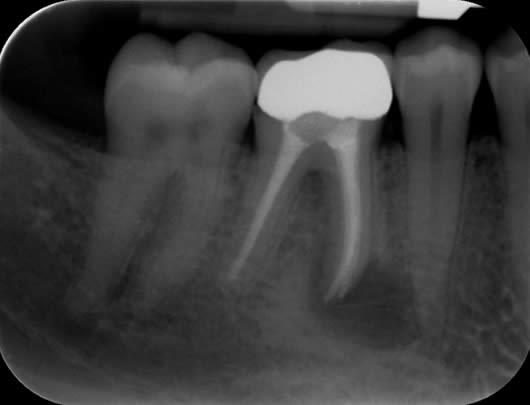

Case 3: Root canal treatment – narrow canals.

As a tooth ages, whether prematurely following trauma or long-term irritation, or in accordance with natural ageing, the root canals can become narrower due to the laying down of further dentine (tooth structure). This can make the canals difficult to locate and very challenging to negotiate to full length. As with finding the elusive MB2 canal (Case 2), we use our experience and the use of the dental microscope to conservatively remove tooth tissue in just the right areas to locate these canals. This cases shows a tooth (UL6) in which it is difficult to see the canals on the radiograph as they are very narrow. We were able to locate four canals (including the challenging MB2 canal) and prepare and fill them.

Before treatment UR6

Following root canal treatment UR6